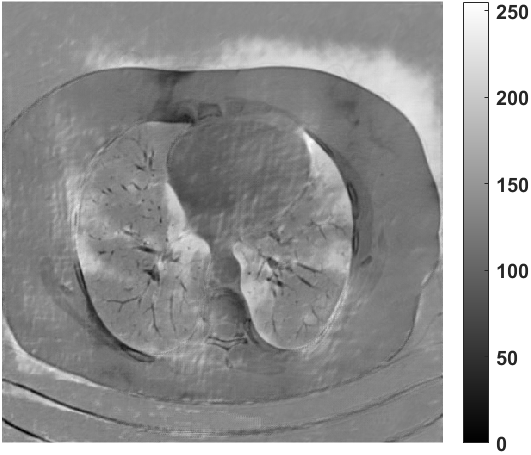

Fig. 4 presents the reconstruction results and residual images obtained by different methods for limited-angle reconstruction. As can be seen, the learning-based methods outperform the direct method and TV model, which exhibit serious artifacts in the missing angle region. Although the denoiser introduced by the FBP-Unet can somehow deal with the noises, the result still presents obvious artifacts. Compared to the SIPID, PD-net and FSR-nets, our LRIP-net1/2 can better preserve the image details and edges with less information left in the residual images. Thus, both the quantitative and qualitative results confirm that the low-to-high double-resolution strategy can improve the reconstruction accuracy for the limited-angle reconstruction problem.

We observe that the low-resolution image prior plays an important role in our method. More specifically, we compare the results of our LRIP-net with respect to different low-resolution priors, which are obtained by down-sampling rate of 1/2, 1/4, and 1/8, respectively. As can be seen in Table III, the best reconstruction results are obtained with the image prior reconstructed by the down-sampling rate of for 150∘, 120∘ and 90∘ limited-angle reconstruction. The visual comparison based on different image priors are also provided in Fig. 5, where obviously less artifacts are left in the reconstruction image by LRIP-net1/8. By comparing the running time, it is easy to see that the smaller the low-resolution image prior, the faster the LRIP-net works.